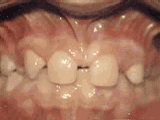

牙列稀疏,牙槽骨过长,或者牙齿少,导致排列太宽松,零零散散,经过矫正后的是这样的~

牙列稀疏,牙槽骨过长,或者牙齿少,光头强就是这类。导致排列太宽松,零零散散,经过矫正后的是这样的~